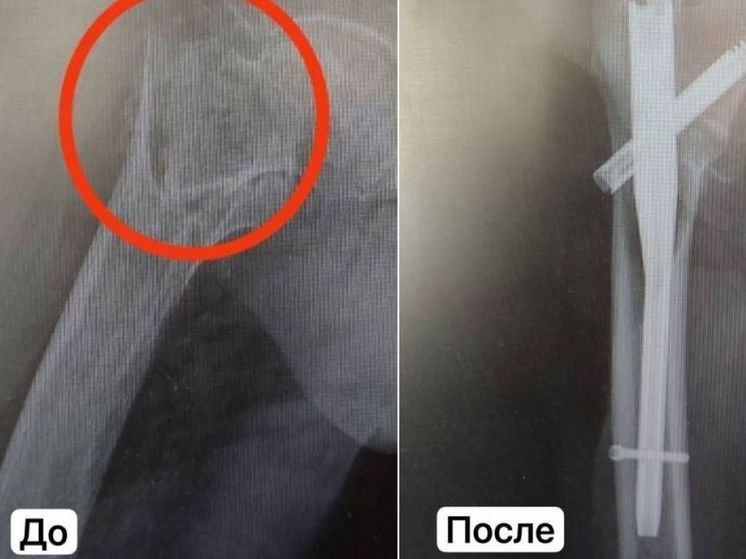

Каширские медики смогли поставить на ноги 101-летнюю женщину с переломом бедра, сообщает пресс-служба Минздрава Подмосковья.

На скорой в больницу Каширы доставили 101-летнюю пациентку после падения. В результате диагностики у женщины обнаружили перелом правой бедренной кости со смещением. Пациентке грозило инвалидное кресло. Однако медики восстановили подвижность долгожительницы.

Пациентке сделали малоинвазивную операцию по фиксированию кости специальным штифтом. Период после хирургического вмешательство прошел без осложнений. Уже на вторые сутки женщина смогла передвигаться самостоятельно с помощью дополнительной опоры. Швы сняли через две недели. Лечение подобных травм у пациентов такого солидного возраста требует от врачей настоящего мастерства и должной квалификации. Только благодаря искусству анестезиологов и травматологов Каширской больницы пациентку удалось поставить на ноги, прокомментировал заведующий отделением Константин Смирнов. В настоящее время женщина уже выписана и передвигается самостоятельно. После успешной операции она смогла вернуться к прежнему образу жизни.